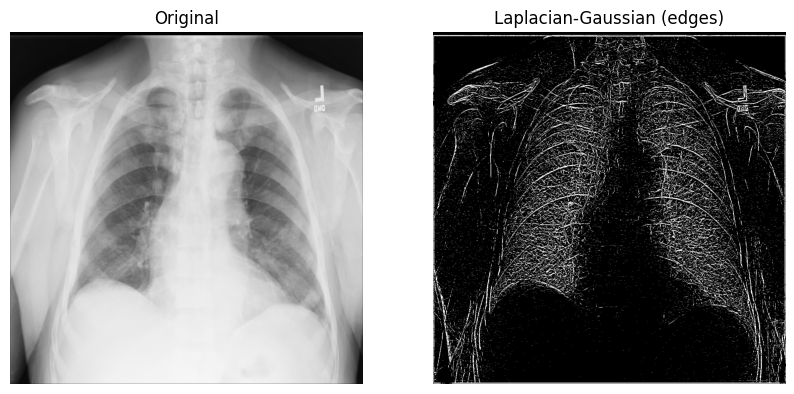

带高斯二阶导数的拉普拉斯滤波器¶

让我们从一个n维拉普拉斯滤波器(“拉普拉斯-高斯”)开始,它使用高斯二阶导数。这种拉普拉斯方法关注像素强度值快速变化的区域,并与高斯平滑结合以去除噪声。让我们看看它在分析2D X光图像方面有多大用处。

拉普拉斯-高斯滤波器的实现相对直接:1)从SciPy导入

ndimage模块;2)调用scipy.ndimage.gaussian_laplace()并设置一个sigma(标量)参数,该参数影响高斯滤波器的标准差(在下面的示例中您将使用1)。

from scipy import ndimage

xray_image_laplace_gaussian = ndimage.gaussian_laplace(xray_image, sigma=1)显示原始X光片和应用了拉普拉斯-高斯滤波器的X光片

fig, axes = plt.subplots(nrows=1, ncols=2, figsize=(10, 10))

axes[0].set_title("Original")

axes[0].imshow(xray_image, cmap="gray")

axes[1].set_title("Laplacian-Gaussian (edges)")

axes[1].imshow(xray_image_laplace_gaussian, cmap="gray")

for i in axes:

i.axis("off")

plt.show()